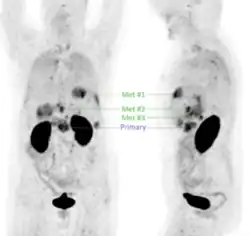

Positronenemissionstomographie (PET) einer Patientin mit Pankreaskarzinom, welche unter Verwendung des Radiotracers 68Ga-Trivehexin erhalten wurde (dargestellt sind Maximalintensitätsprojektionen aus frontaler und seitlicher Blickrichtung). Deutlich sichtbar ist der Primärtumor (Primary) sowie mehrere Lebermetastasen (Met).

Neuere Forschungen setzen sich intensiv mit der Anwendung der Positronen-Emissions-Tomographie (PET) für die Bildgebung des (duktalen) Pankreaskarzinoms (PDAC) auseinander, wobei das Interesse insbesondere auf die Detektion von Metastasen fokussiert ist. Für PET ist die intravenöse Gabe eines Radiotracers erforderlich, also eines Radiopharmakons, welches mit einem Positronen emittierenden Radionuklid markiert ist. Der für die PET am häufigsten eingesetzte Tracer, 18F-Fluordesoxyglucose (FDG) ist jedoch für die Diagnostik des PDAC nur bedingt geeignet, da dessen vergleichsweise langsames Wachstum und die desmoplastische Gewebsstruktur oft dazu führt, dass FDG zu gering angereichert wird, um eine verlässliche PET-Diagnostik zu gewährleisten.[43] Die Tumorzellen von PDAC weisen jedoch in den meisten Fällen (>88 %) eine Überexpression des Oberflächenproteins αvβ6-Integrin auf, weshalb Radiopharmaka, die spezifisch an dieses Protein binden, für die PET-Bildgebung von PDAC genutzt werden können.[44] Im Zuge der experimentellen klinischen Anwendung verschiedener αvβ6-Integrin-gerichteter Radiotracer zeigte sich, dass 68Ga-Trivehexin[45] gut für die PET-Bildgebung des metastatischen PDAC geeignet sein könnte (siehe Beispielbild), insbesondere aufgrund der vergleichsweise geringen unspezifischen Anreicherung im gastrointestinalen Bereich.[46] Infolgedessen wurde 68Ga-Trivehexin experimentell für die PET-Bildgebung in einigen PDAC-Fällen[47][48][49] sowie einer größeren Kohorte (44 Patienten)[50] mit PDAC oder Verdacht auf PDAC erfolgreich diagnostisch angewendet.